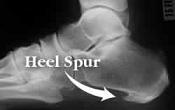

درمان خار پاشنه کلینیک تخصصی پا - تهران

ايا مي دانيد موثرترين و تنها راه درمان خار پاشنه استففاده از كفي طبي ارتوپدي مي باشد ؟

با استفاده از كفي هاي فانكشنال ارتوپدي براي هميشه و در كوتاه ترين زمان و با كم ترين هزينه

از خار پاشنه و درد پاشنه رها شويد.